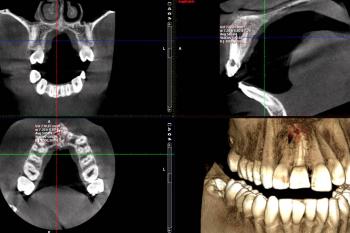

Vatech American Pax-i3D Imaging Unit

Conventional intra-oral radiography provides clinicians with cost-effective, high-resolution imaging that continues to be the front-line method for dental imaging. However, it is clear that there are many specific situations where the 3-D images produced by CBCT facilitates diagnosis and influences treatment. The usefulness of the CBCT cannot be disputed. It is a valuable task-specific imaging modality, producing minimal radiation exposure to the patient and providing maximal information to the clinician.